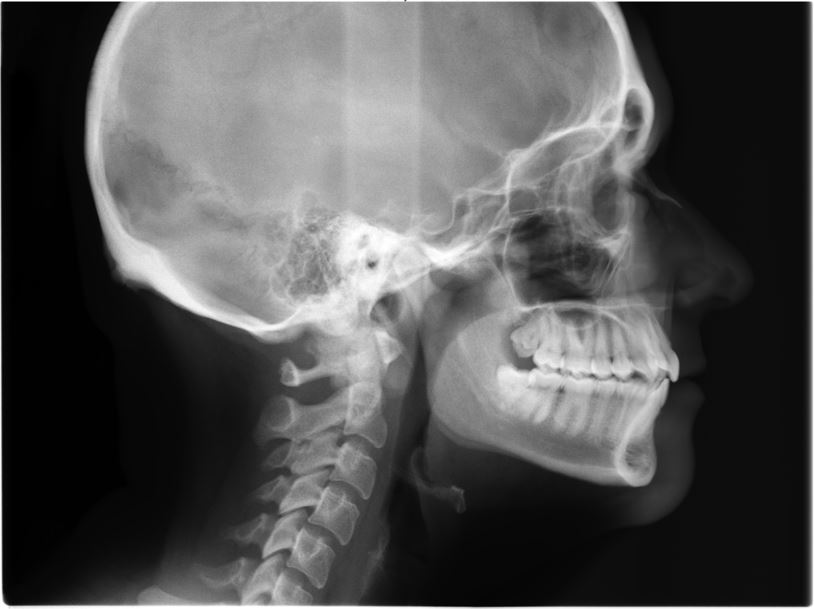

This is not the only thing cephs can tell us, though! This specific x-ray can also show us where the patient is in their stage of growth. Do you see the vertebrae in the x-ray above? Each one has a bit of a curve to it towards the bottom: this indicates the end of this patient's growth stage! If the vertebrae are more squared off, the patient is still experiencing stages of growth, which you can see in the example below.

Through the ceph above, we can see that this patient still has some growth spurts to look forward to, but not only does this particular ceph show the patient's growth, we can also see their airway. A huge benefit of cephs is the ability to see a patient's adenoids and their relation to a patient's airway, as seen in the image to the right.